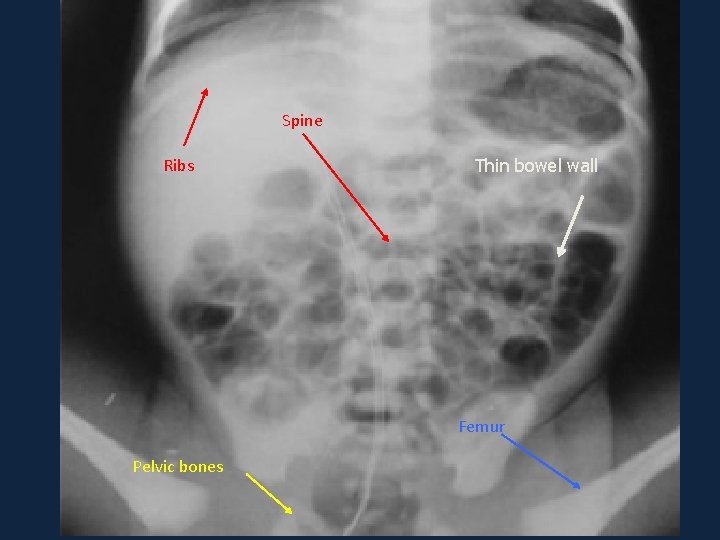

Systematic approach ►A ►Bone and Bowel: ►C Bones: ribs, pelvis, femur, ►D spine. ►E Bowel: Thorough look at the bowel dilatation from stomach to rectum

Spine Ribs Thin bowel wall Femur Pelvic bones